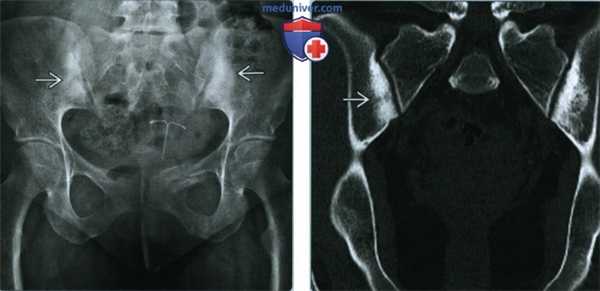

(Слева) Рентгенография в ПЗ проекции: у молодой женщины, обследованной в связи с травмой, был случайно обнаружен конденсационный остеит подвздошных костей. Наблюдается двусторонний склероз крыльев подвздошных костей, ограниченный областью, прилегающей к крестцово-подвздошному сочленению. Область склероза имеет форму, приближенную к треугольной, с верхушкой направленной краниально.

(Справа) КТ, корональный срез: треугольная форма области склероза подвздошных костей, четко определяющая границы аномалии.

(Слева) КТ, аксиальный срез: у этой же пациентки подтверждается расположение склерозированной области в пределах крыльев подвздошных костей и щажение крестца и крестцово-подвздошных сочленений. Дополнительная визуализация или дальнейшее наблюдение при конденсационном остеите не требуются.

(Справа) КТ, костное окно, аксиальный срез: у пациента с болью выше правого грудинно-ключичною сочленения определяется диффузный склероз головки правой ключицы. Грудина (изображение не представлено) сохранна. Других поражений скелета выявлено не было. Ведущим предварительным диагнозом является конденсационный остеит ключицы.